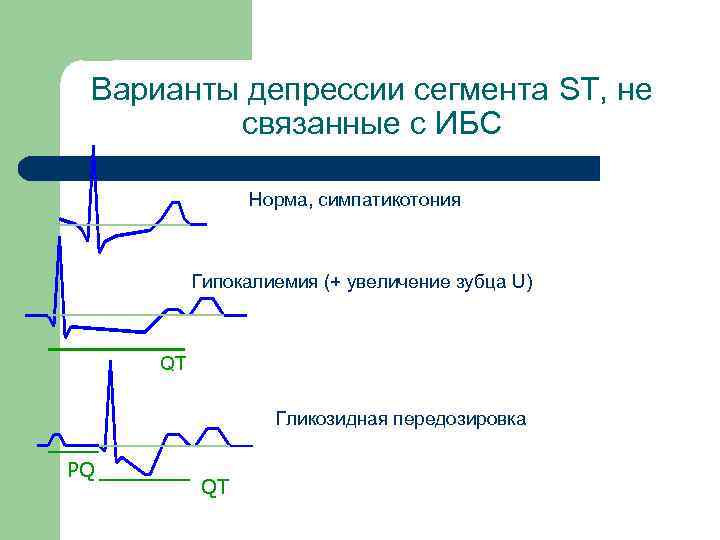

Варианты депрессии сегмента ST, не связанные с ИБС Норма, симпатикотония Гипокалиемия (+ увеличение зубца U) QT Гликозидная передозировка PQ QT